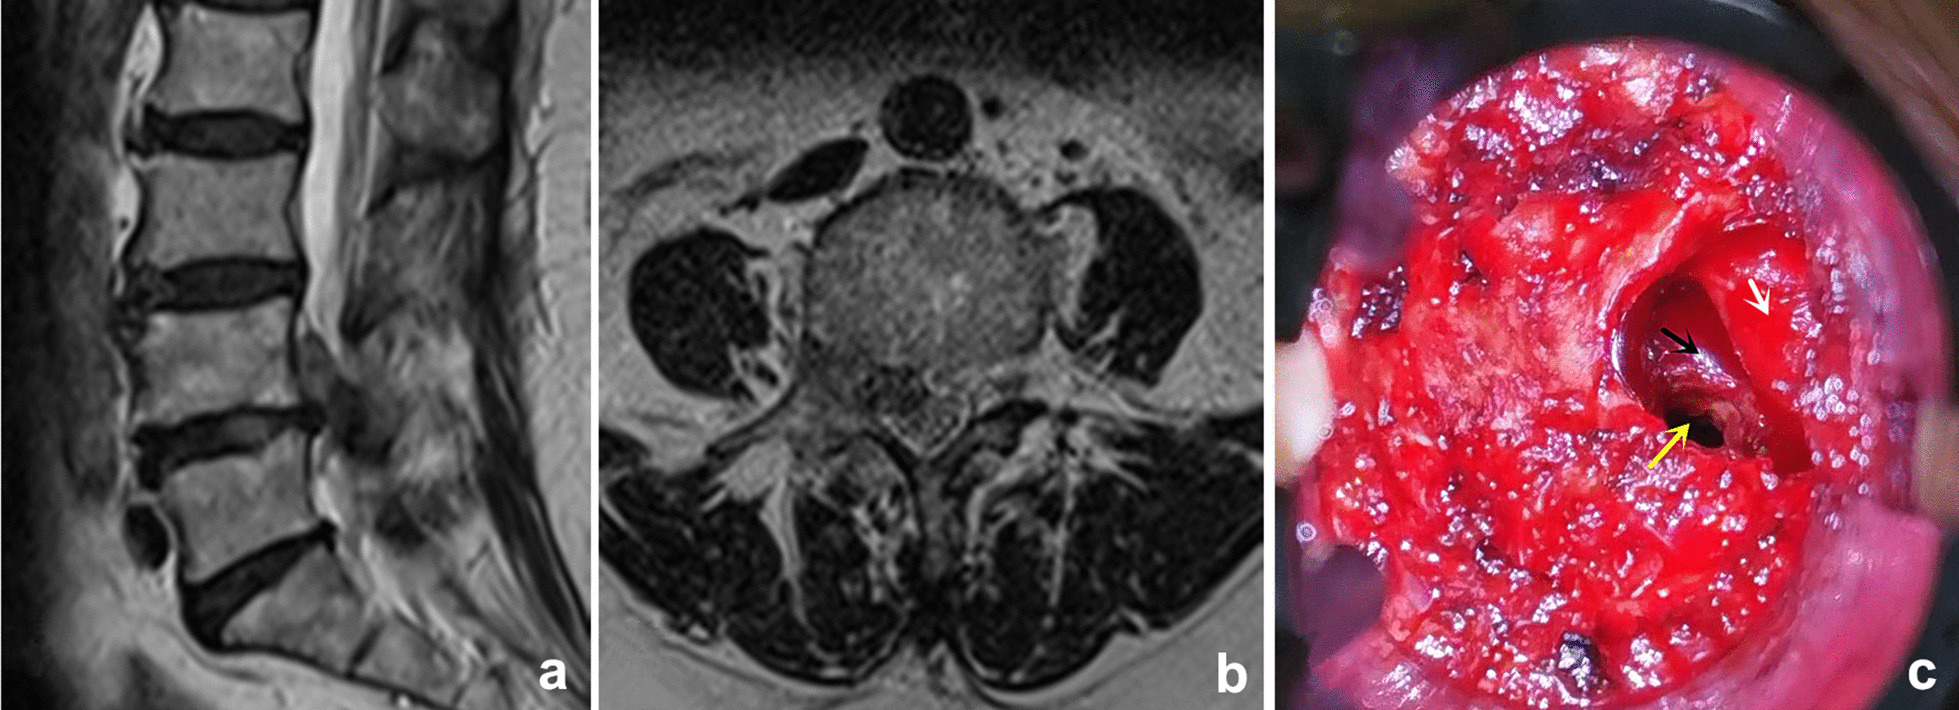

Fig. 3.

a, b The preoperative MRI showed the migrated fragments were obviously linked with the inferior disc. c The intervertebral space can also be approached after removing a small part of the IAP (white arrow: exiting nerve root; black arrow: posterior wall of vertebral body; yellow arrow: intervertebral space)